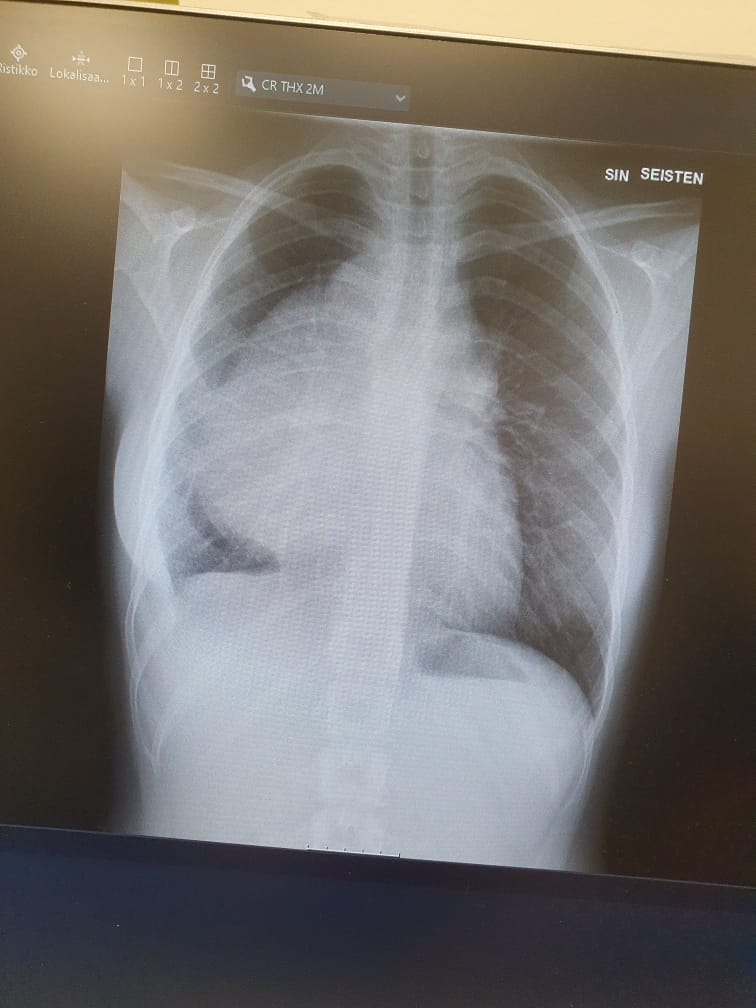

Jyllilän röntgenkuvassa kasvain näkyy vasemmalla rintakehässä.

Vitsailu loppui kun lääkäri kertoi Jyllilän keuhkojen välikarsinasta löytyneen kolme sinne kuulumatonta pattia.

Kasvainta ei voitu poistaa leikkaamalla, sillä se sijaitsi liian lähellä sydäntä ja oli kietoutunut verisuonien ympärille.